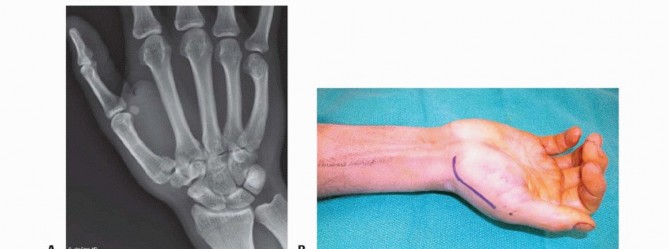

Our imaging protocol must be exhaustive to provide a three-dimensional understanding of the fracture morphology. Standard hand radiographs are insufficient due to the unique 30-degree pronated position of the thumb relative to the rest of the carpus. A True AP View of the Thumb CMC Joint (Robert's view) is obtained with maximal forearm pronation, placing the dorsum of the thumb flat on the cassette. This optimizes visualization of the joint space and the critical ulnar fragment. The True Lateral View (Billing and Gedda) is achieved with the hand pronated 20 degrees and the thumb flat on the cassette, with the X-ray beam tilted 10 degrees from vertical in a distal-to-proximal direction.

Patient Positioning and Operating Room Setup

Proper patient positioning is critical for unhindered surgical access and seamless fluoroscopic imaging. The patient is placed supine on the operating table with the affected extremity extended onto a radiolucent hand table. A well-padded upper arm tourniquet is applied to ensure a bloodless surgical field, which is absolutely essential for identifying small articular fragments and protecting delicate neurovascular structures.

Open Reduction and Internal Fixation (ORIF) - Wagner Approach

For fractures with large volar-ulnar fragments (>20% of the articular surface), displaced Rolando fractures, or cases where closed reduction fails, ORIF is unequivocally mandated. The classic Wagner approach provides unparalleled exposure to the thumb CMC joint. A curvilinear incision is made along the glabrous border of the thenar eminence, curving dorsally at the level of the CMC joint.

Meticulous superficial dissection is required to identify and protect the sensory branches of the superficial radial nerve dorsally and the palmar cutaneous branch of the median nerve volarly. The thenar musculature (abductor pollicis brevis and opponens pollicis) is sharply elevated from the metacarpal shaft and retracted volarly. The joint capsule is then incised longitudinally or in an L-shaped fashion to expose the articular surface. The hematoma is evacuated, and the fracture fragments are meticulously debrided of interposed soft tissue.